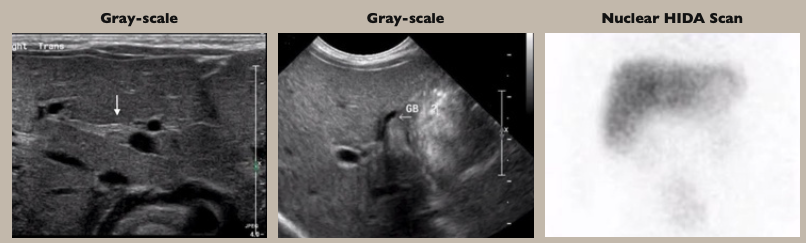

• 초음파검사

• 담낭 내강이 보이지 않거나, 작은 담낭 ( <1.5 cm)

• triangular cord sign: portal vein 의 anterior에서 보이는 echogenic fibrous tissue의 두께 ≥4mm 인 소견. 담관의 섬유화 잔재

• HIDA: neonatal hepatitis와의 감별에 사용, 간에서의 uptake은 보이나, 시간이 지나도 담도로 담즙배설이 나타나지 않음.

왼쪽 : normal HIDA scan. 간 uptake → biliary excretion → 소장에서의 uptake 확인

가운데: biliary atresia. 간에서의 uptake은 보이나 시간이 지나도 담도/소장으로의 배출이 확인되지 않음

오른쪽: Neonatal hepatitis. 간에서 uptake이 보이고, 수시간이 지난 후 소장으로의 배출이 확인됨